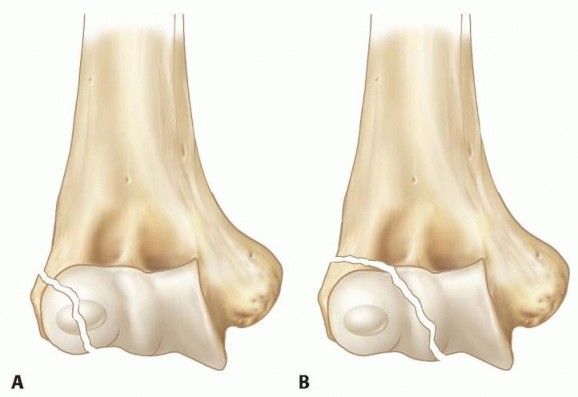

The Milch classification stratifies fractures based on the exit point of the fracture line through the distal articular surface:

* Milch Type I: The fracture line passes lateral to the trochlear groove, traversing the ossific nucleus of the capitellum. This represents a true Salter-Harris IV fracture. The lateral trochlear ridge remains intact and attached to the humeral shaft, thereby maintaining relative radioulnar stability and preventing lateral subluxation of the radius.

* Milch Type II: The fracture line passes medial to the capitellar ossific nucleus, exiting through the apex of the trochlear groove. This represents a Salter-Harris IV equivalent (though radiographically it may mimic a Salter-Harris II if the trochlea remains unossified). Because the critical lateral trochlear ridge is fractured and mobilized with the condylar fragment, the radius and ulna lose their lateral buttress and can subluxate laterally. This renders Milch Type II fractures inherently unstable.

- Milch (1964): Established the fundamental anatomic classification system, highlighting the critical biomechanical importance of the lateral trochlear ridge in maintaining global elbow stability. Milch Type II fractures are inherently more unstable due to the loss of this essential articular buttress.